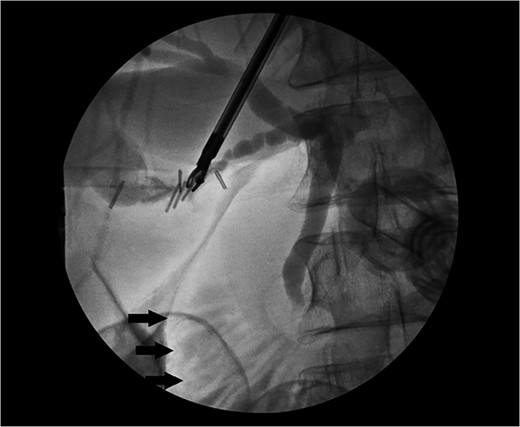

She received normal saline boluses, intravenous piperacillin-tazobactam and vancomycin, and was admitted for sepsis secondary to suspected cholangitis or cholecystitis. Magnetic resonance cholangiopancreatography found no evidence for common bile duct stone, cholecystitis or biliary ductal dilatation. Two blood cultures drawn on admission showed gram-negative rods, so piperacillin-tazobactam was continued. Due to the likelihood of a biliary source for sepsis, laparoscopic cholecystectomy with intraoperative cholangiogram was performed revealing an inflamed gallbladder with multiple stones and no filling defects on cholangiogram (Fig. 3). Gallbladder pathology was consistent with chronic cholecystitis with cholelithiasis and AMH (Fig. 4). The blood cultures and an intraoperative bile culture both grew R. planticola (Fig. 5), which was susceptible to ciprofloxacin. The patient recovered well from her surgery and was discharged home with a 2-week course of oral ciprofloxacin.

Intraoperative cholangiogram with contrast within the cystic, common hepatic and common bile duct with no filling defect to suggest choledocholithiasis. Contrast can be seen within the duodenum (arrows).